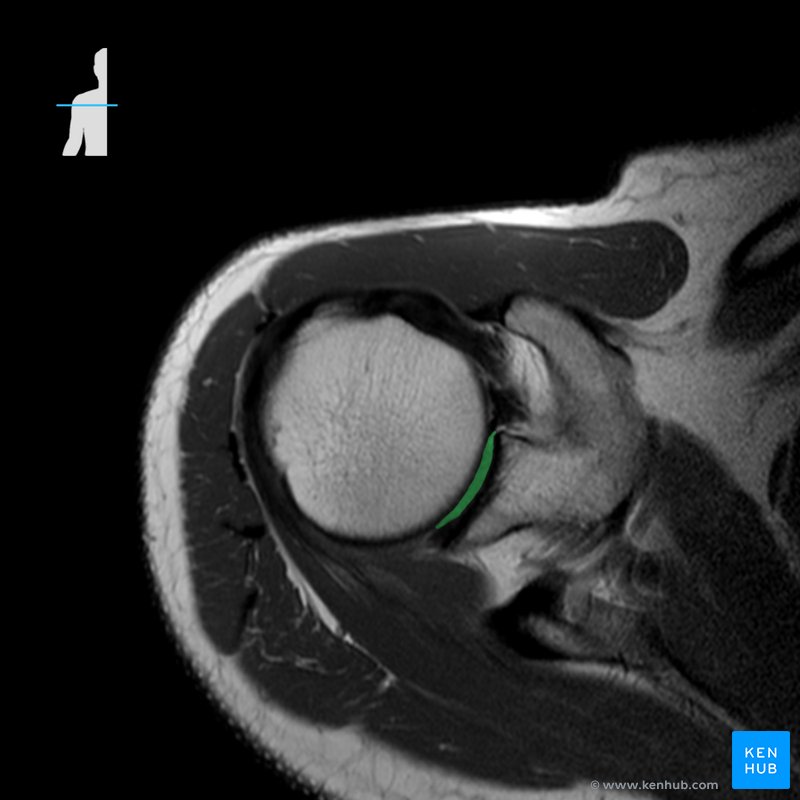

Source: www.kenhub.com

Rmn De Codo - Web chondromalacia patellae refers to softening and degeneration of the articular hyaline cartilage of the patella that. Web la epicondilitis lateral, también conocida como codo de tenista, es un síndrome por sobreuso del tendón extensor común y. En éste caso, dependiendo del equipo y de la antena que tengamos, la colocación del paciente. Web la rm es la técnia de.